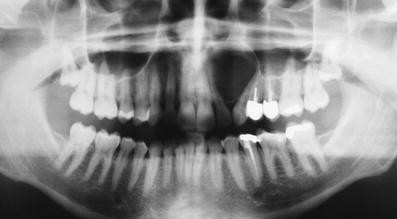

| – Cyst between maxillary lateral incisor and adjacent canine. – Inverted pear-shaped radiolucency. -Can diverge adjacent teeth roots. |